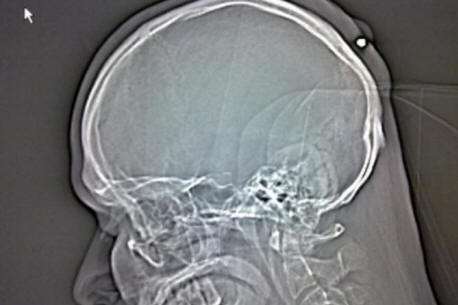

Když se odvolával na nemocnici, Autullo tomu odmítl uvěřit lékaři mu to ukázali: na rentgenovém snímku to bylo jasné osm centimetrů železného hřebíku uvíznutého přímo uvnitř lebky krabice od Dante. Před sanitkou vzal Autullo na jinou kliniku operaci, Dante zveřejnil fotografii, že na jeho Facebook stránce RTG snímek.